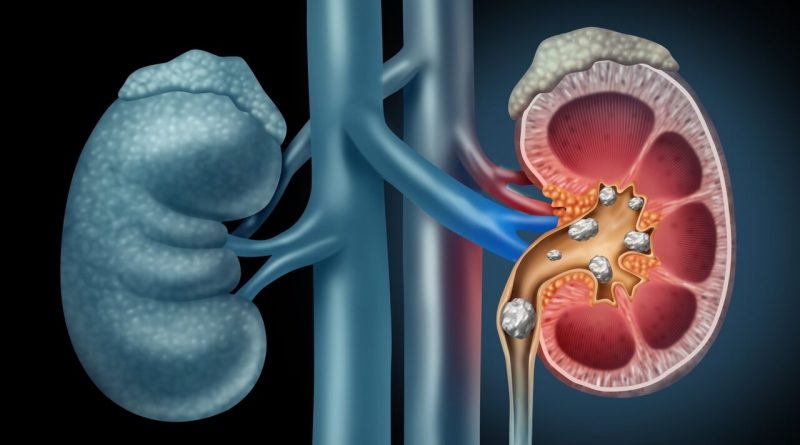

سنگ کلیه زمانی ایجاد می شود که مواد معدنی مانند کلسیم، اگزالات و فسفات در مجاری کلیه متمرکز و به کریستال تبدیل می شوند. اگر می خواهید از تشکیل این سنگ ها پیشگیری کنید، باید از علل ابتلا به این سنگ ها آگاه باشید. در اینجا ۱۰ علت شگفت انگیز که خطر ابتلا به این عارضه را تشدید می کنند، معرفی شده است: